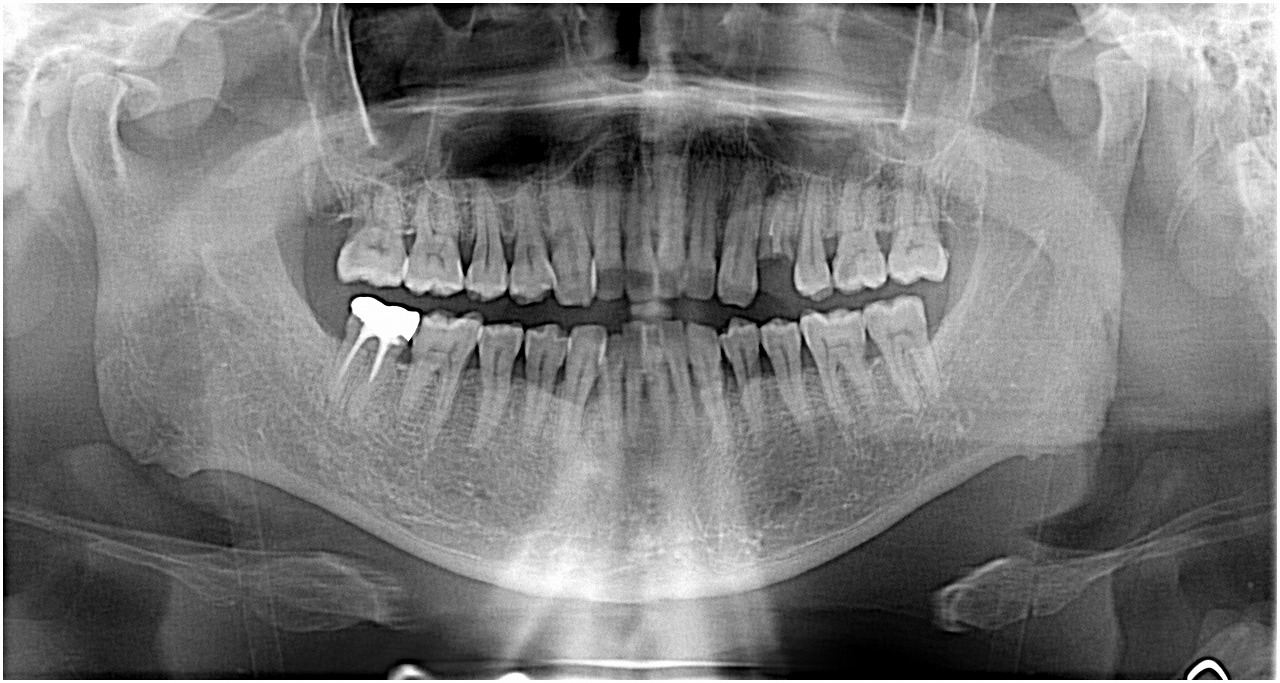

術前のパノラマになります